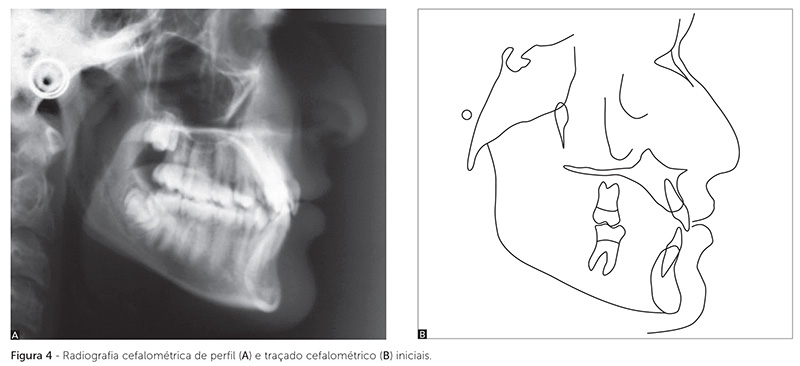

Na radiografia cefalométrica de perfil e traçado cefalométrico (Fig. 4), verificou-se um padrão esquelético equilibrado, no sentido anteroposterior, entre maxila, mandíbula e demais estruturas faciais (ANB = 1° e Ang. Convexidade = -0,5°), com padrão de crescimento e plano mandibular predominantemente horizontais (SN-GoGn = 25°, FMA = 20° e Eixo Y = 54°). Os incisivos superiores e inferiores estavam retroinclinados (1-NA = 20°, 1-NA = 6mm, 1-NB = 7°, 1-NB = 4mm e IMPA = 83,5°). Esses e os demais valores cefalométricos estão apresentados na Tabela 1.